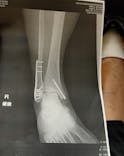

1 / 5段階中プールから上がってシャワー浴びる所で滑って、足を骨折してしまいました。全治数ヶ月のことで大変困っています。ただ、注意書きもなく滑りに注意の放送もなかったのが不安です。さらに、骨折したに...ひろ投稿日 4